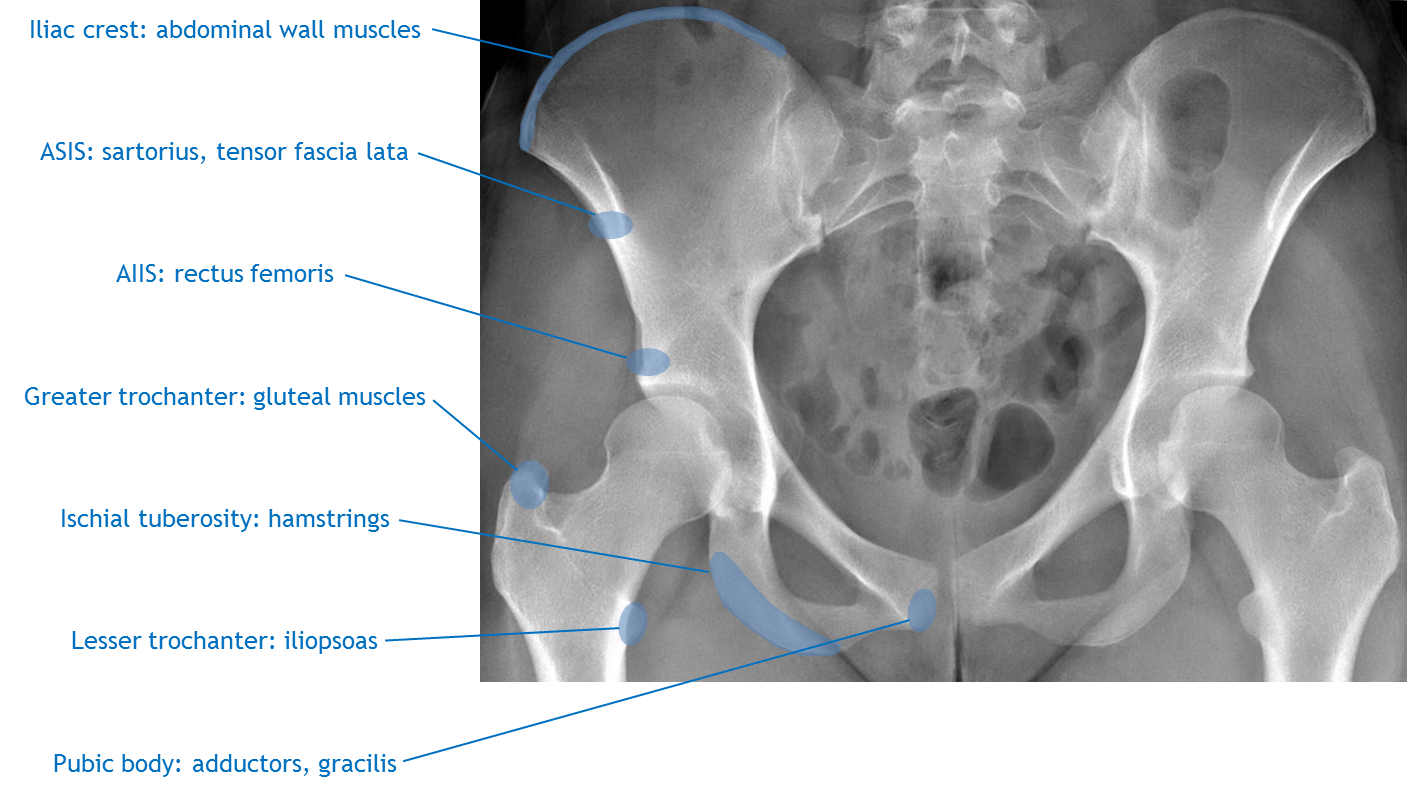

Pelvic Apophyseal Avulsion Fractures Diagram | Image | Radiopaedia.org

Pelvic apophyseal avulsion fractures diagram | Image | Radiopaedia.org radiopaedia.org

avulsion pelvic iliac apophyseal radiology spine anterior fractures diagram superior hip muscle injury radiopaedia anatomy fracture pelvis pain apophysis ray